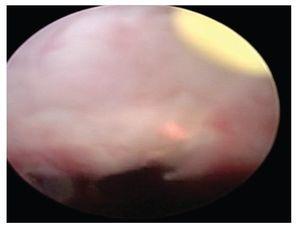

Se seleccionaron las patologías endourológicas más frecuentes realizadas en nuestro Servicio. El primer caso se trata de una paciente femenina de la quinta década de la vida, sin antecedentes crónico degenerativos, que se presenta por cólico pieloureteral izquierdo. Al interrogatorio dirigido refería cólico intermitente anual, desde hace más de cinco años. Durante su abordaje diagnóstico, se realizó radiografía simple de abdomen en donde se observó imagen radiopaca en silueta renal izquierda a nivel de la pelvis renal. En el ultrasonido renal (USG) se observó dilatación pielocaliceal importante, por lo que se realizó gammagrama renal con diurético y MAG (mercaptil acetil triglicina), observándose FPER del 30%. Por tomografía computada (TAC) se evidenció imagen hiperdensa además de estenosis de la unión ureteropiélica (UP) (Figura 1). Por lo cual, se llevó a endopielotomía mediante ureteroscopía flexible con laser Holmium fibra de 200nm (Figura 2), más nefrolitotripsia también con laser Holmium fibra de 200nm a 16W, con técnica de fragmentación directa (Figura 3) y colocación de catéter ureteral doble J ipsilateral.

Figura 1. Ureteroscopía flexible. Se observa estenosis puntiforme de unión ureteropiélica (UP) izquierda, canulada con una guía metálica.

Figura 2.Endopielotomía laser (HLEP): Incisión mediante laser Holmium en estenosis de la unión ureteropiélica (UP), corte a las seis horas a 16W.

Figura 3. Nefrolitotripsia con laser de Holmium de lito en pelvis renal, de 12 milímetros aproximadamente.